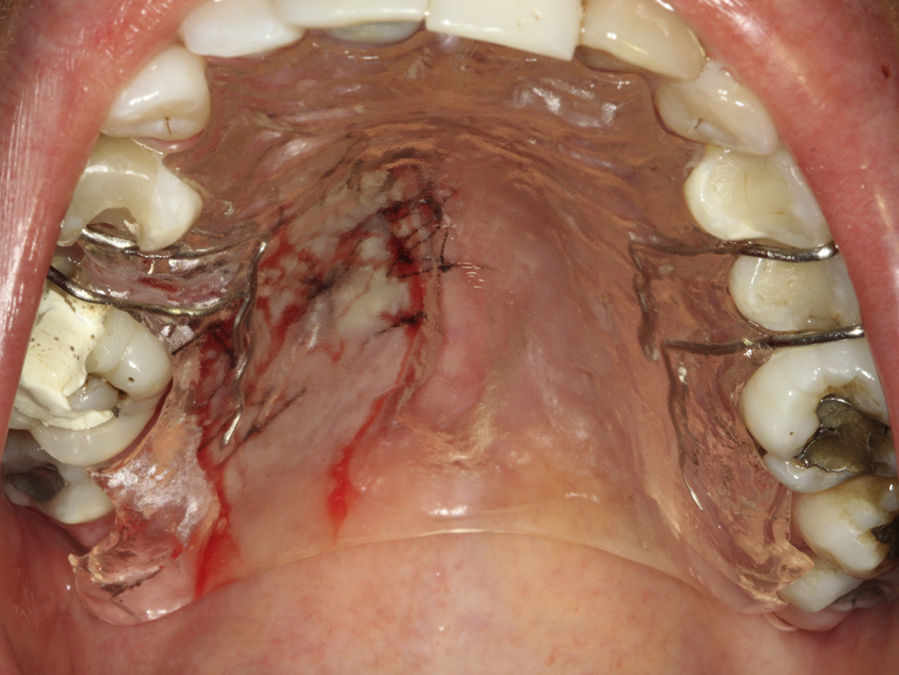

Paciente do sexo feminino, 31 anos de idade, leucoderma, foi encaminhada pelo cirurgião‐dentista à Clínica de Estomatologia do Departamento de Odontologia da PUC Minas para avaliação de lesão nodular no palato duro com diagnóstico histopatológico de adenoma pleomórfico, obtido por meio de biópsia incisional. Durante a anamnese, a paciente relatou a evolução da lesão há 4 anos com característica assintomática. Relatou estar no sexto mês de gestação e não apresentava outras alterações sistémicas. O exame extraoral mostrou ausência de alterações. Ao exame intraoral, observou‐se um aumento de volume bem delimitado no palato duro do lado direito, de consistência firme e coloração semelhante à da mucosa normal, medindo aproximadamente 2,5cm, exibindo pequena área de ulceração no local da realização da biópsia incisional (fig. 9). O exame radiográfico não mostrou alterações. O tratamento proposto foi a remoção cirúrgica conservadora e confecção de placa palatina em acrílico com grampos retentores para minimizar o desconforto pós‐operatório. Foi realizada anestesia local com lidocaína 2% e epinefrina 1:100.000 (ALPHACAINE 100®, DFL, Rio de Janeiro, Brasil), seguida de incisão semilunar com bisturi lâmina 15 (Solidor, São Paulo, Brasil) e rebatimento do retalho mucoso. Como a lesão se apresentava encapsulada, foi possível destacá‐la da mucosa suprajacente com facilidade (fig. 10). O retalho foi reposicionado por meio de pontos isolados (fig. 11) e a lesão (fig. 12) foi fixada em formaldeído a 10% para realização de exame anatomopatológico no Laboratório de Patologia Bucal da PUC Minas. Em seguida, foi colocada a placa de acrílico (fig. 13) para proteção da região operada e controlo da sintomatologia dolorosa.